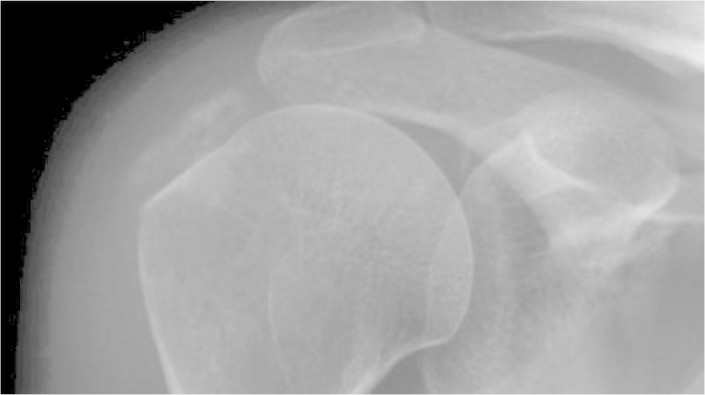

Figure 1.

A) AP radiograph with internal rotation of the shoulder; B) AP radiograph with external rotation of the shoulder; and C) Lateral scapular radiograph of the shoulder.

Figure 2.

Calcification of the supraspinal tendon, of length 1.5 cm.

A retrospective study was conducted on 20 patients who had undergone arthroscopic treatment for calcifying tendinitis of the shoulder between March 1999 and October 2006. Six patients were excluded because of loss of follow-up. Thus, in March 2006, 14 patients of mean age 55 years (range: 37 to 72 years) were reevaluated. Eight of them (57%) were male and six (43%) were female. The right side was affected in nine patients (64%) and the left side in five (36%). All of them presented calcifications in the tendon of the supraspinatus (Table 1). Radiographs were produced in anteroposterior view with neutral, external and internal rotations of the shoulder, in true lateral view of the shoulder, and in axillary lateral view of the shoulder and supraspinal tunnel (Figure 1). The size of the calcifications was measured in millimeters along their major axis using a standard ruler graduated in millimeters. All the calcifications (100%) were greater than or equal to 5 mm in length and were classified as large (greater than 1.5 mm), according to the Bosworth classification(14) (Figure 2).